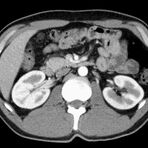

Abdomen (Bauch und Becken)

• Diagnostik von entzündlichen und tumorösen Erkrankungen der Bauchorgane

• Diagnostik von akuten Notfällen wie Darmverschluss, Hohlorganperforation oder Traumafolgen

• Darstellung der großen Gefäße zur Erkennung von Gefäßverschlüssen (z. B. Mesenterial - Arterienembolie oder Einengungen von Gefäßen (z. B. Nierenarterien)

• Darstellung und Therapieplanung von Aneurysmen (CT- Angiographie)